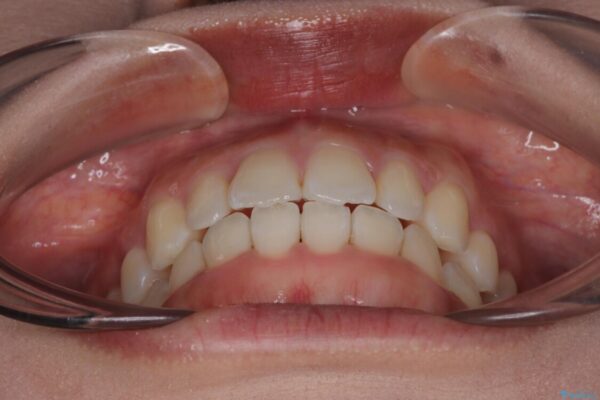

前歯のデコボコが気になるでのことで来院された患者様です。

歯列アーチが狭くスペース不足により前歯がデコボコしている状態でした。見た目を改善しつつ、前歯を前方に突出させず、自然な笑顔を目指したいというご希望でした。

治療前

• 目立ちにくい表側装置で1年完了!狭いアーチを側方拡大し前歯のデコボコを整えた症例 治療前画像